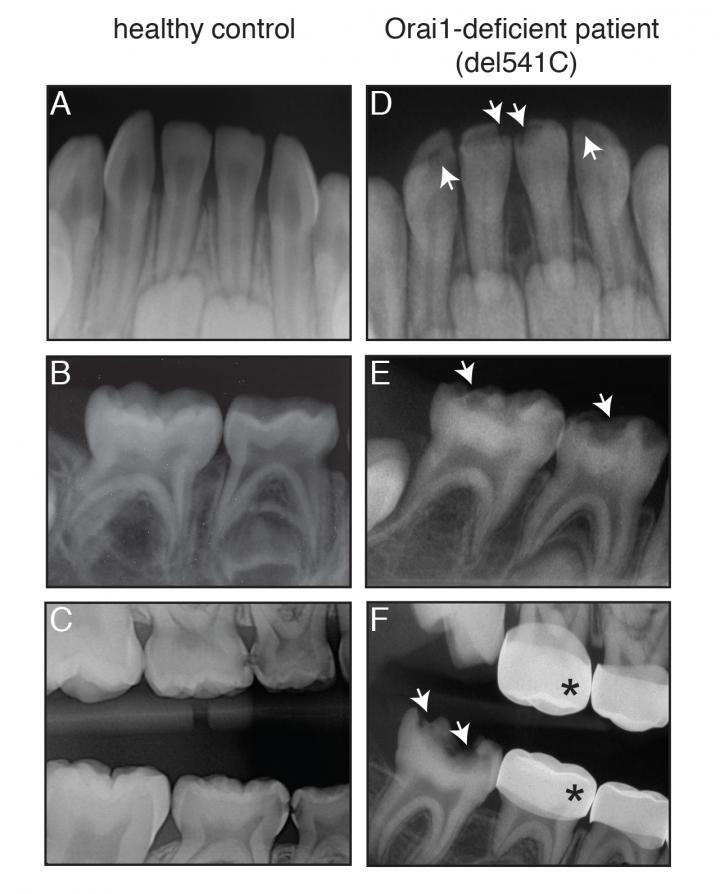

image: X-rays from an 8-month old patient with Orai1 deficiency. The patient had abnormal, pitted teeth due to defects in enamel (white arrows). This material relates to a paper that appeared in the Apr. 23, 2019, issue of Science Signaling, published by AAAS. The paper, by M. Eckstein at New York University College of Dentistry in New York, NY; and colleagues was titled, "Differential regulation of Ca 2+ influx by ORAI channels mediates enamel mineralization." view more

Credit: M. Eckstein <i> et al., Science Signaling </i> (2019)